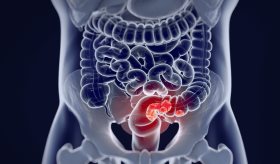

Este análisis genético ofrece nuevas pistas sobre los mecanismos que impulsan el cáncer colorrectal, en este caso, hábitos como el tabaquismo y el consumo frecuente de alcohol, además de algunas bacterias del aparato digestivo pueden estar relacionadas con alteraciones genéticas que causan cáncer.